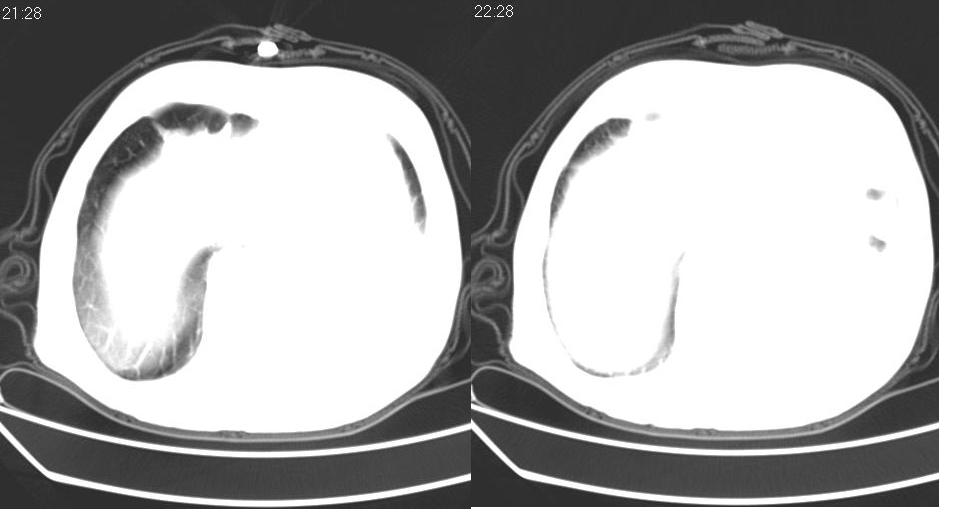

1、左肺下叶后基底段炎症并膨胀不全。

2、左侧胸腔积液。

3.两肺慢支改变。

左下肺体积缩小,密度增高,并见大片状致密影,边界模糊,其内见支气管充气像,肺门纵隔无异常,心脏气管左移,左侧胸腔少量积液。考虑:左肺炎性病变伴不张。

左肺下叶感染,肺膨胀不全,左胸腔积液,不能排除结核性病变